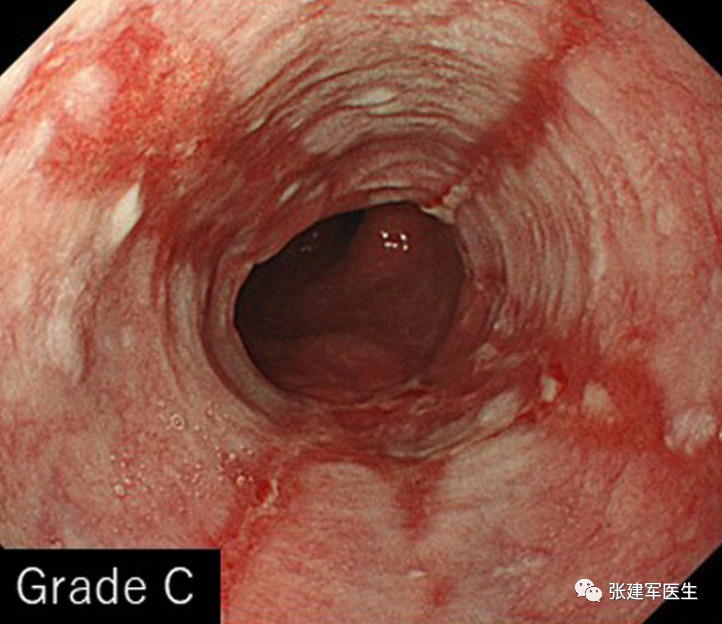

食道炎(Esophagitis),食道中的酸会导致食道内壁发炎。 慢性炎症会导致疼痛、吞咽问题、溃疡甚至出血。

胃十二指肠镜检查

能直观评估食管、胃以及十二指肠粘膜状态,诊断糜烂性食管炎及巴雷特食管(Barrett's esophagus),明确食管裂孔疝的大小及类型,确定食管裂孔疝有无扭转。